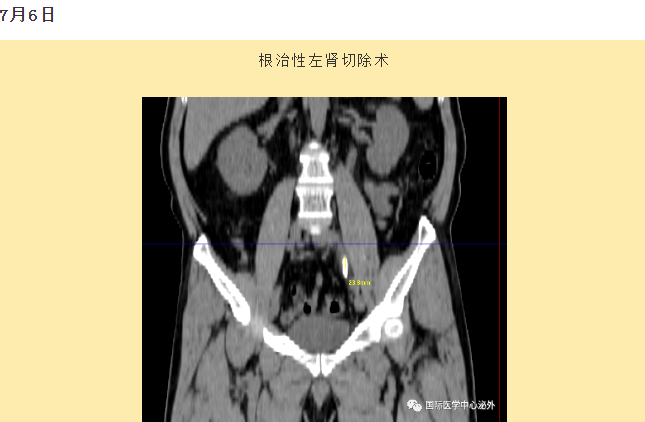

西安國際醫(yī)學(xué)中心醫(yī)院順利完成了達芬奇Xi(第四代)機器人裝機。7月6日—7月15日,泌尿外科成功完成了達芬奇Xi(第四代)機器人手術(shù)6例,標志著科室微創(chuàng)外科邁入新時代,造福萬千患者。